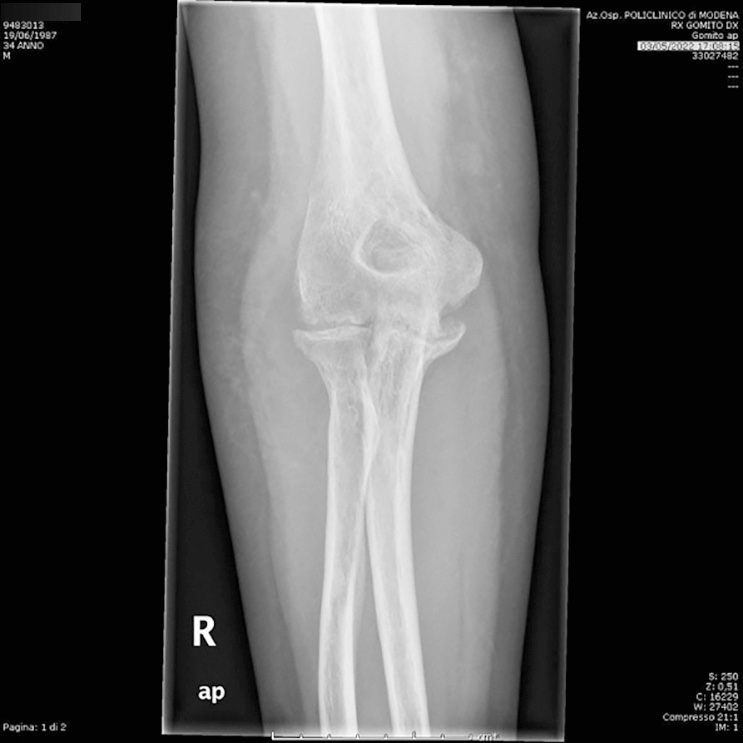

Sebbene l’incidenza annuale degli impianti eseguiti per le artriti infiammatorie stiano diminuendo, l’artrite reumatoide è ancora presente ed è l’indicazione più comune con esiti favorevoli (Fig. 1).

L’indicazione principe alla protesi di gomito nei pazienti con patologie infiammatorie come l’AR è il dolore, che spesso si trova accompagnato da rigidità, deformità e perdita di sostanza ossea, instabilità articolare. Nell’ambito della traumatologia, invece, oltre alle protesi totali di gomito, posso optare anche su emiartroprotesi, osteosintesi e tecniche conservative fino alla “bag of bone”. La scelta si basa sulla complessità della frattura e sulla base della specifica superficie articolare dell’ulna prossimale e/o dell’omero distale che ha perso di continuità: colonna mediale, troclea laterale, capitulum o totale. Le controindicazioni specifiche comprendono tutte le condizioni patologiche di avambraccio e mano che ne causano grave compromissione della funzionalità. Infezioni attive o recenti, uno scarso trofismo cutaneo o cicatrici retraenti nella regione del gomito potrebbero causare un’insufficiente copertura dei tessuti molli ed elevato rischio di deiscenza, necrosi cutanea e scarsa mobilizzazione post-impianto. L’intervento di protesi di gomito è spesso controindicato in pazienti giovani con elevate richieste funzionali.